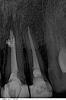

Shubova Опубликовано 10 мая, 2011 Автор Поделиться Опубликовано 10 мая, 2011 (изменено) конечно! этот снимок был сделан после первой пломбировки. Двойка в работе. Изменено 10 мая, 2011 пользователем Shubova Ссылка на комментарий

silver77 Опубликовано 19 мая, 2011 Поделиться Опубликовано 19 мая, 2011 Добрый день!После повторно запломбированного канала (единица) ( впервый раз пломбировочный материал слишком сильно вышел за верхушку канала, врач приняла решение переделывать) образовалась шишка в области крыльев носа и онемение. Созвонилась с врачем, говорит это от пасты, может рассосется, может нет. Но нужно делать резекцию корня. Верно ли было проведено лечение?http://s005.radikal.ru/i210/1105/3a/694b18a57915.jpghttp://s002.radikal.ru/i198/1105/4a/10e1feb9f405.jpgесть ленточная перфорация (протертая дыра-место перфорации оставил белого цвета)и канал не допломбирован до нужного уровня-"шишка" и проблемы от того,что остались микробы ,живущие в канале,на которых организм не в силах повлиять.То место ,где раньше выходил нерв ,даже по рентгену видно, необходимо пломбировать МТА потому что этот самый выход очень большого размера....... и перфорацию тоже закрыть МТА(иначе потеряете зуб)Вам необходим специалист,который работает с микроскопом и владеет необходимыми методиками...он Ваш спаситель.Рисунок-красное - границы стенок зуба зеленое - пломбировочный материал белое - инфекция Ссылка на комментарий